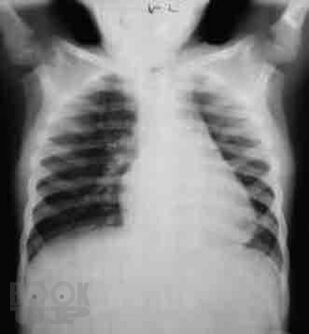

Сборник включает вызвавшие наибольший интерес аудитории лекции и доклады на различных научно-практических конференциях в 2017–2018 гг. по актуальным проблемам пульмонологии и аллергологии детского возраста, таким как: современные методы диагностики и лечения, острые и хронические инфекционно-воспалительные и аллергические заболевания органов дыхания, муковисцидоз, туберкулез органов дыхания, а также обмен опытом, интересные случаи из медицинской практики, различные другие информационные материалы. Ежегодник адресован практикующим детским пульмонологам и аллергологам.